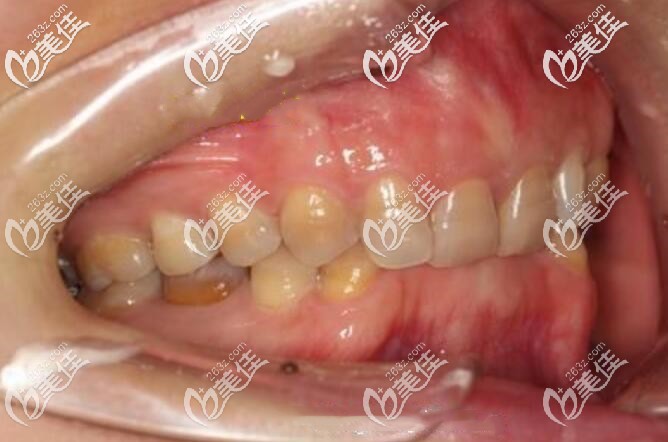

我的深覆合不矫正越来越厉害了:

我不清楚被人的深覆合不矫正将来会咋样,但是我的后果已经挺厉害了,再耽搁下去,我怕我的下牙就要“全军覆没”了。

我属于闭合性深覆合,就是上前牙内扣,下牙列都抵住上牙硬腭粘膜,一咬就疼,下牙牙冠都快磨没了,牙周状况特差,属于再不整,这口牙就要报废了。